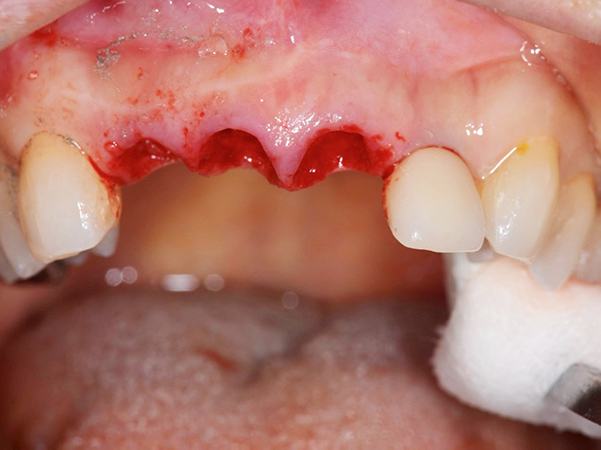

1次手術時の流れ

①手術開始時

②被せ物を外した状態

③抜歯

④サージガイドを使用したインプラント体の埋入

⑤インプラント体を埋入した状態

⑥仮歯を製作していく段階

⑦仮歯を装着した状態

埋入したばかりのインプラント体に負担がかからないように、下の歯と当たらないような形と噛み合わせになるよう調整しています。